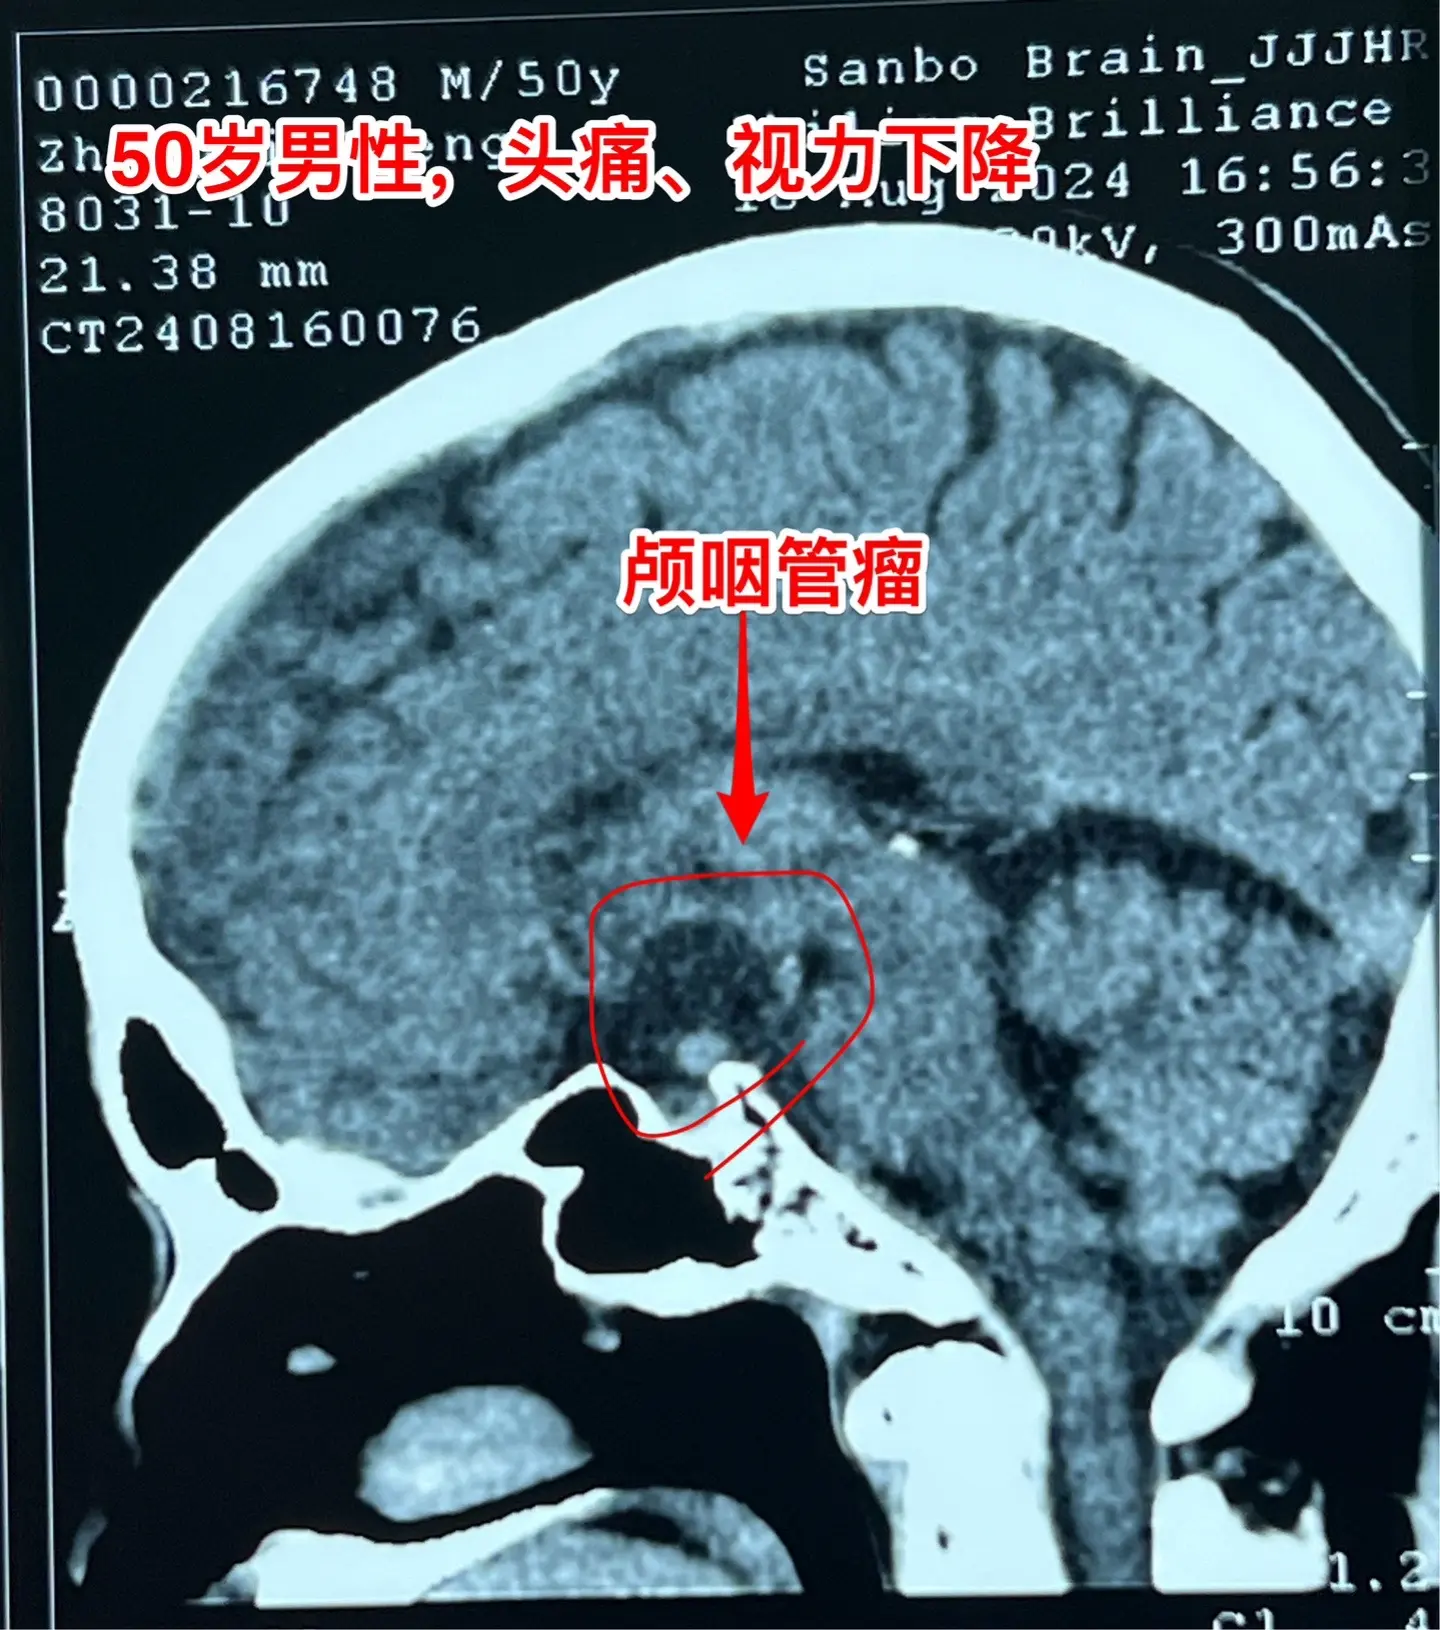

颅咽管瘤手术,出院3天就开车,合适吗?50岁的山东临沂男性,因头痛一年,左眼视力下降三个月于2024.8.16在我科住院。左眼视力0.1,右眼视力1.0。8月22日行开颅手术切除颅咽管瘤,手术后视力改善,身体恢复顺利,9月2日出院了,出院前测左眼视力0.5,右眼1.0。出院时精神好,体力好。 9月8日患者女儿和我联系,说患者出院三天就开车了。我告诉她,需要复查视力和视野,如果视野有缺损,开车是有风险的,不适合开车。